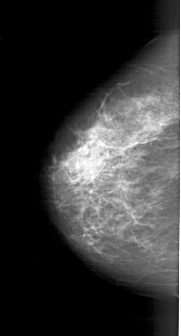

A_1771_1.RIGHT_MLO

RIGHT_MLO LINES 6091 PIXELS_PER_LINE 3451 BITS_PER_PIXEL 12 RESOLUTION 43.5 OVERLAY